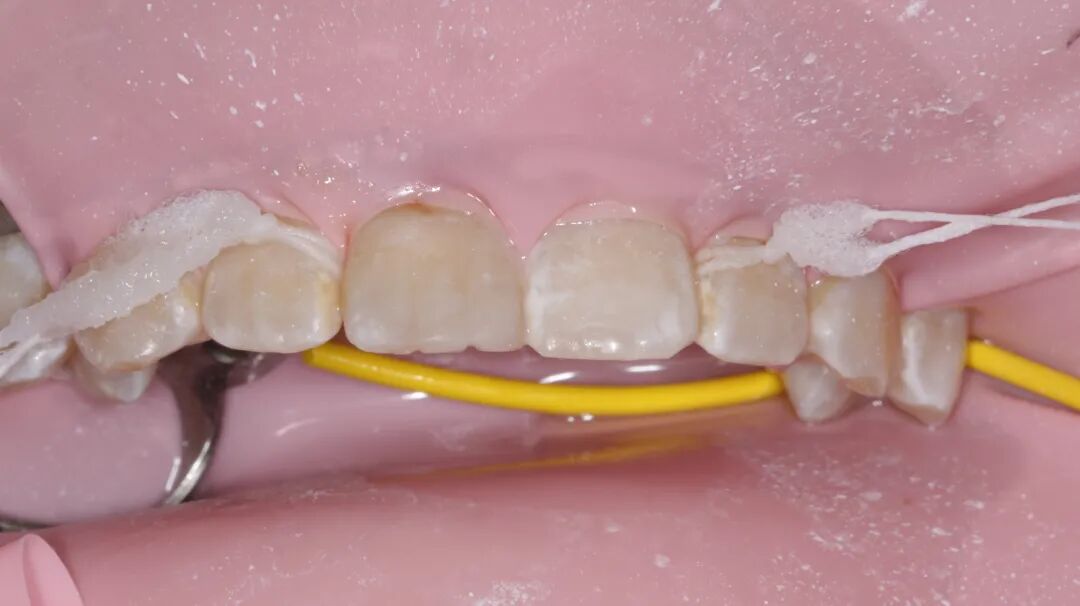

牙医-李子豪【实操病例】

患者女,16岁

主诉:半年前因外伤导致右上1牙体缺损,现暑假期间自觉不美观,今日与家长来我院就诊

检查:口内右上1近中切角折断,患牙不松动,牙髓活力正常。因患者年龄较小,家长不接受冠修复,沟通后选择树脂修复。取术前观测模型,蜡恢复缺损部位,制作硅橡胶导板。橡皮障夹配合【康田正楔线】障下修整缺损面,【康田正消毒刷】涂布自酸蚀粘接剂,放置导板,流体树脂恢复舌侧基本形态,【康田正豆瓣成形片】恢复邻接形态后唇面常规树脂充填,修型,调合,抛光,康田正邻面抛光条抛光邻面。